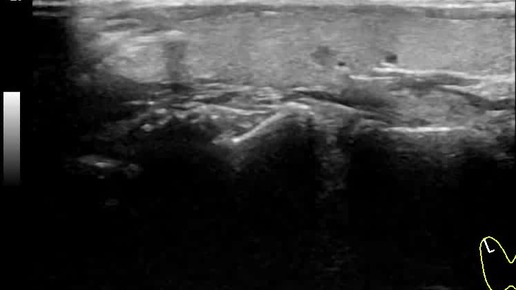

Видео к статье "Стратификация узлов щитовидной железы. TI-RADS-3" https://dzen.ru/a/Zv4svErHVi-eImKZ

Ультразвуковые находки от врача УЗД Зорина Я.П.